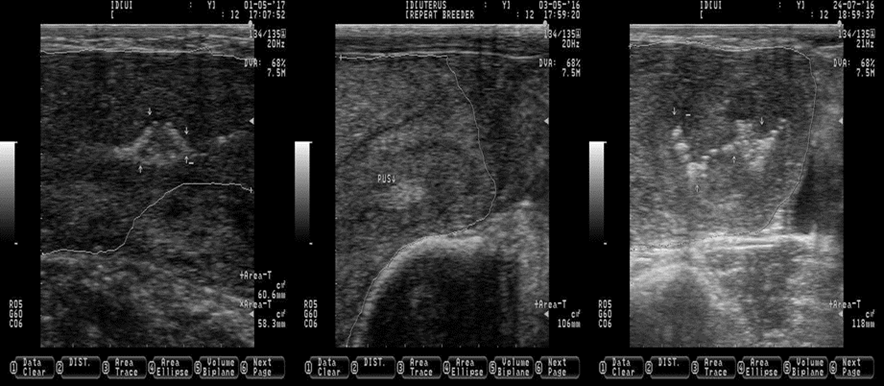

White arrows indicating the location of pus (the pus is observed as bright and white spots of different shapes and sizes). White lines are delimiting the uterine horns. Pictures were taken using a 7.5 MHz probe.

Figure 9 Pictures depicting the presence of pus (subclinical endometritis) in the uterus of Holstein dairy cattle at random stages of lactation